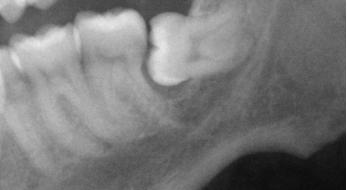

Any kind of infection or abscess in the jaw can cause cavitational osteonecrosis. For me my worst problem was caused by how my lower wisdom teeth grew. Below is an x-ray of my original problem.

You can actually see visible bone loss under the tooth. This bone has been destroyed by infection. What you can't see is, infection has killed the bone in almost that entire area.